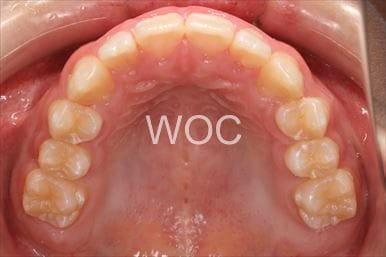

治療後1

- 年齢:20歳女性

- 主訴:出っ歯が気になる

- 基本矯正料金:120万円

- 治療期間:1年7ヶ月

- 抜歯部位:上顎両側第一小臼歯